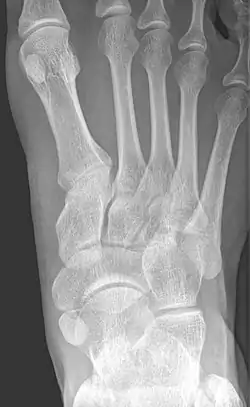

X-ray of the foot showing an accessory navicular bone

An accessory navicular bone is an accessory bone of the foot that occasionally develops abnormally in front of the ankle towards the inside of the foot. This bone may be present in approximately 2-21% of the general population and is usually asymptomatic.[1][2][3] When it is symptomatic, surgery may be necessary.